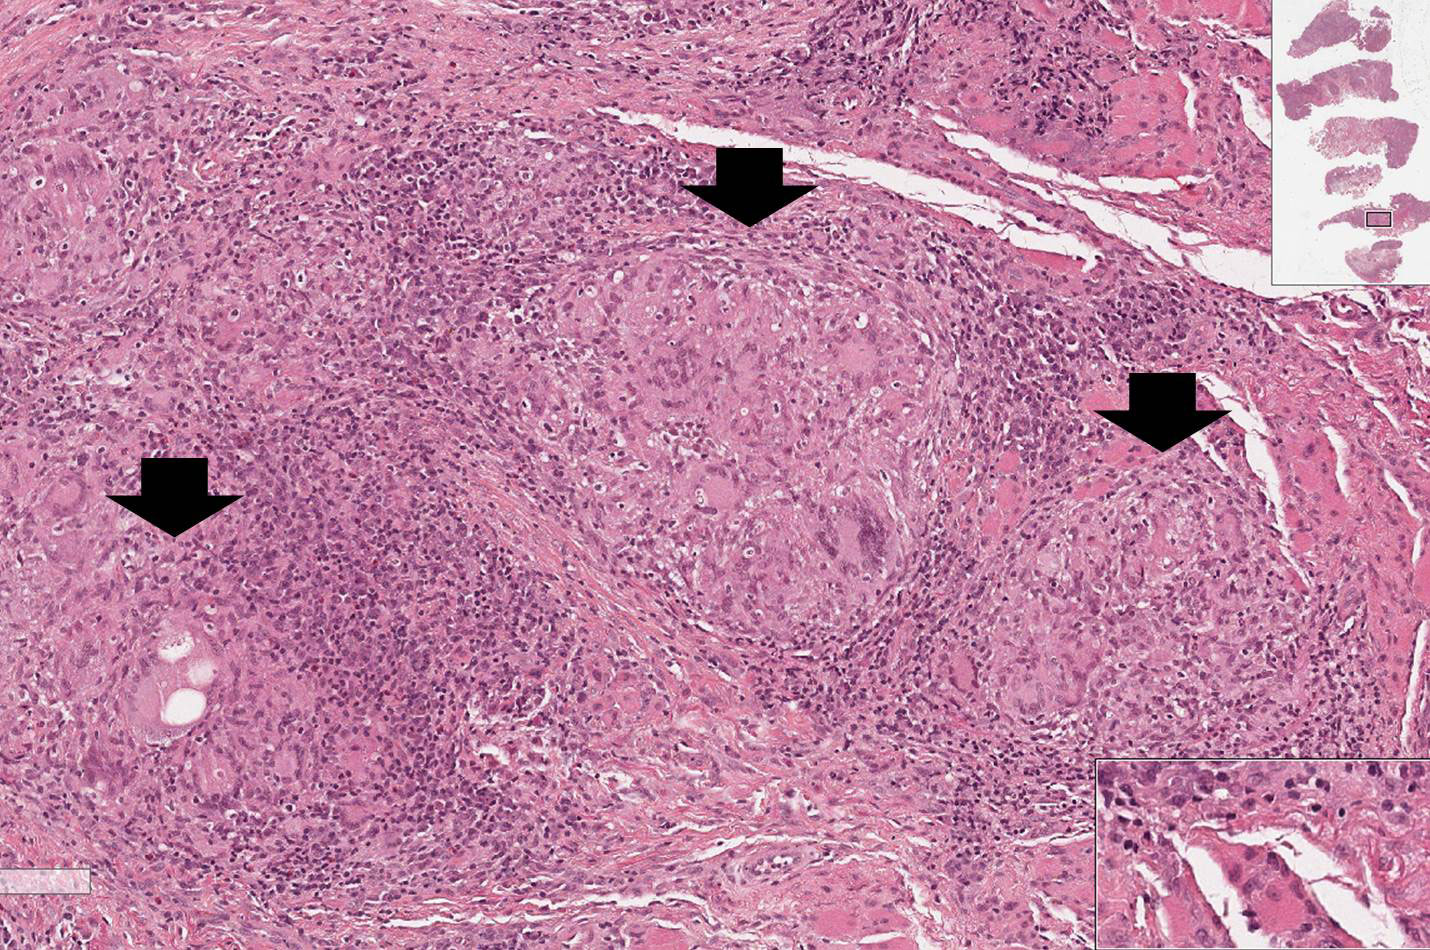

Doença infecciosa crônica causada pela Mycobacterium tuberculosis.

Fragmento de tecido pulmonar no qual parte da arquitetura alveolar é preservada enquanto em algumas regiões demonstram a formação de granulomas epitelióides caseosos. Na porção superior observa-se um granuloma extenso apresentando áreas de necrose caseosa central (material amorfo com perda de seletividade tintorial), entremeada por macrófagos epitelióides (núcleo claro e mais alongado, semelhante a morfologia de uma célula epitelial), linfócitos e células gigantes do tipo Langhans (asteriscos amarelos), circundadas por fibroplasia. Na porção dos alvéolos mais preservada também se nota a presença de um granuloma menor sem necrose central, mas apresentando os outros componentes.

Observar a formação dos granulomas compostos por macrófagos epitelióides, células gigantes do tipo Langhans (asteriscos amarelos), linfócitos (asteriscos verdes) e fibroplasia.

Tuberculose